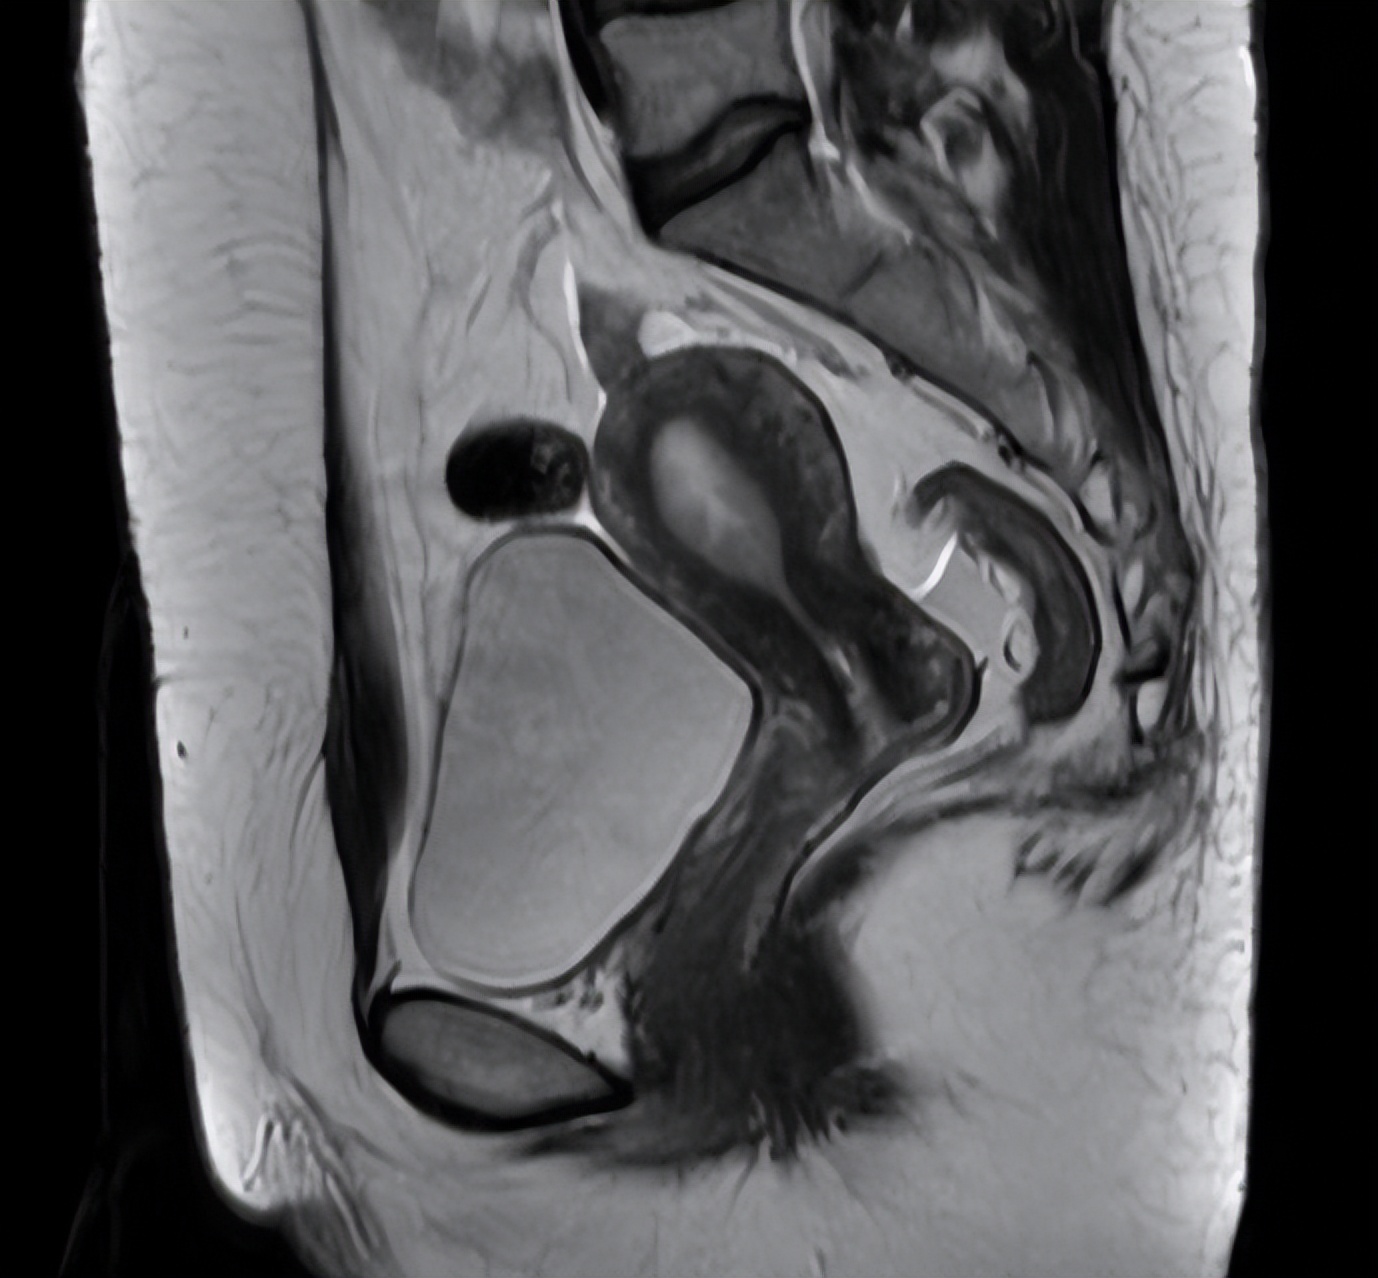

患者的病理会诊结果与外院一致,盆腔核磁提示宫颈占位1.6*1.3*1.1cm,肿瘤标记物CA 199:87.6U/ml。结合门诊查体,考虑诊断宫颈腺癌IB1期,在治疗方案上,患者为年轻女性,手术治疗较放化疗能更好的保留阴道功能。

图片来源 :讲述者提供